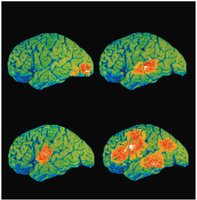

Functional Areas of the Cerebral Cortex

The cerebral cortex is the site of conscious mind activities, including awareness, sensory perception, voluntary motor initiation, communication, memory storage, and understanding. It is a thin (2–4 mm) layer of gray matter covering the cerebral hemispheres.

Three types of functional areas: motor (voluntary movement), sensory (conscious sensation), association (integration of information).

Each hemisphere controls the contralateral side of the body.

Lateralization: specialization of function in one hemisphere (e.g., language in the left hemisphere).

Motor and Sensory Maps

Specific regions of the cortex correspond to control of particular body parts, represented by the motor homunculus (precentral gyrus) and sensory homunculus (postcentral gyrus). These maps illustrate the proportional representation of body regions based on the density of motor or sensory innervation.